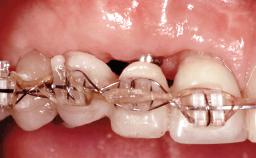

Replacement of Four Incisors with a Fixed Partial Denture on Two Narrow-Neck Implants after Implant Failure

| Loading Protocol | Conventional or early |

| Retention | Screw-retained, with splinted implants Screw-retained, with splinted implants |

| Provisional Implant-Supported Prosthesis | Prosthodontic margin >3 mm apical to mucosal crest Prosthodontic margin >3 mm apical to mucosal crest |

| Interim Prosthesis during Healing | Removable Removable |

| Occlusion/Articulation | Harmonious |